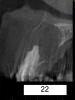

samsonov Опубликовано 7 июля, 2013 Автор Поделиться Опубликовано 7 июля, 2013 Цистэктомия получилась...Простите за качество изображений. 1 Ссылка на комментарий

kriokov Опубликовано 7 июля, 2013 Поделиться Опубликовано 7 июля, 2013 (изменено) нормально все, оболчка толстая, думаю почти везде нормально уходила. Что за мембрана?Нос целый? Изменено 7 июля, 2013 пользователем kriokov Ссылка на комментарий

ПалСаныч Опубликовано 7 июля, 2013 Поделиться Опубликовано 7 июля, 2013 (изменено) Самсонов, последний снимок зачёт!! Сюрреализм))) Надеюсь это не фотошоп))) Изменено 7 июля, 2013 пользователем ПалСаныч 4 Ссылка на комментарий